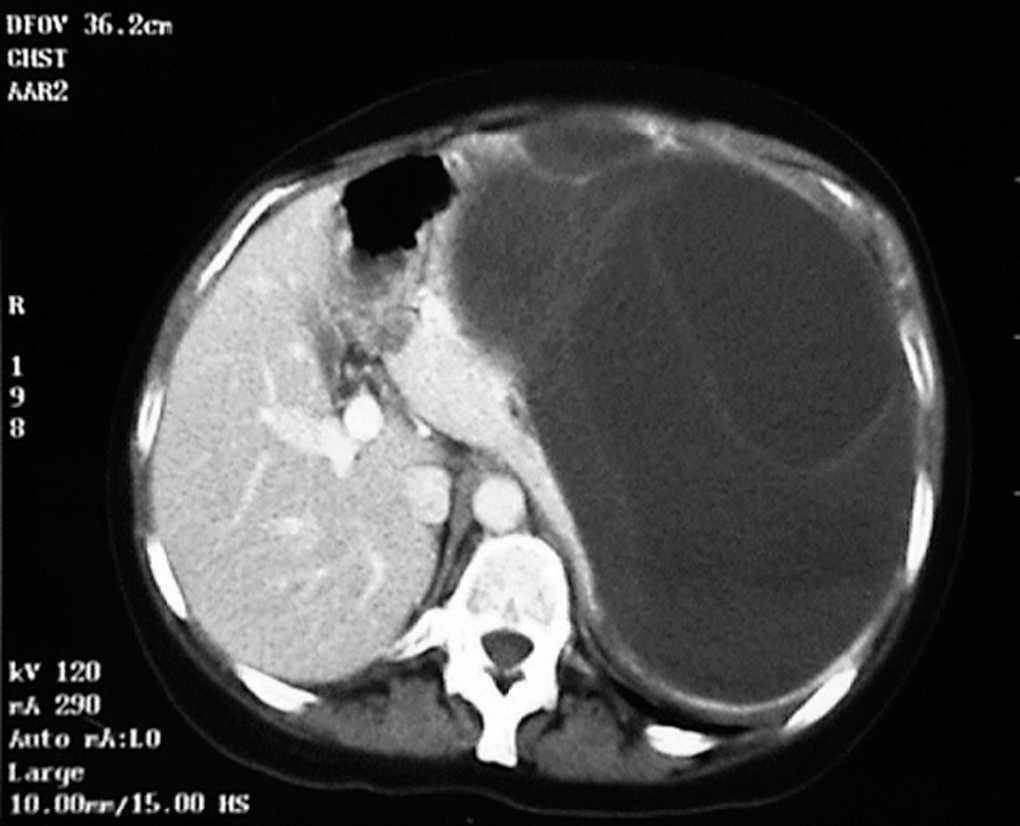

Mujer de 41 años, que consultó por dolor y distensión abdominal progresiva. En la exploración física destacaba la presencia de una tumoración abdominal elástica, no dolorosa, que ocupaba epigastrio, hipocondrio y vacío izquierdos. Las exploraciones complementarias revelaron la presencia de anemia y leucopenia leves y trombopenia. Cabe destacar que la serología de la hidatidosis (hemaglutinación indirecta) fue negativa. Se realizó radiología simple, ecografía y tomografía computarizada (TC) abdominal que demostraron la existencia de una tumoración sólido-quística de 24 cm de diámetro máximo que dependía del bazo (fig. 1), sin la presencia de quistes hepáticos, renales ni pulmonares.

Fig. 1. Tomografía computarizada en la que se observa el quiste hidatídico esplénico que contacta íntimamente con el estómago, el lóbulo izquierdo del hígado, la cola del páncreas y el riñón izquierdo. Destaca la presencia de septos dentro del quiste.